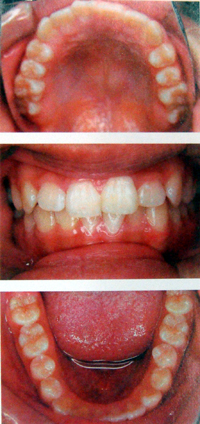

狭く細長い歯並び

舌が収まりきれず、気道を圧迫し、いびきや無呼吸症候群の原因となります。

矯正後

自然に歯が並びます。また、空間ができて、いびき、無呼吸症候群が解消します(個人差があります)